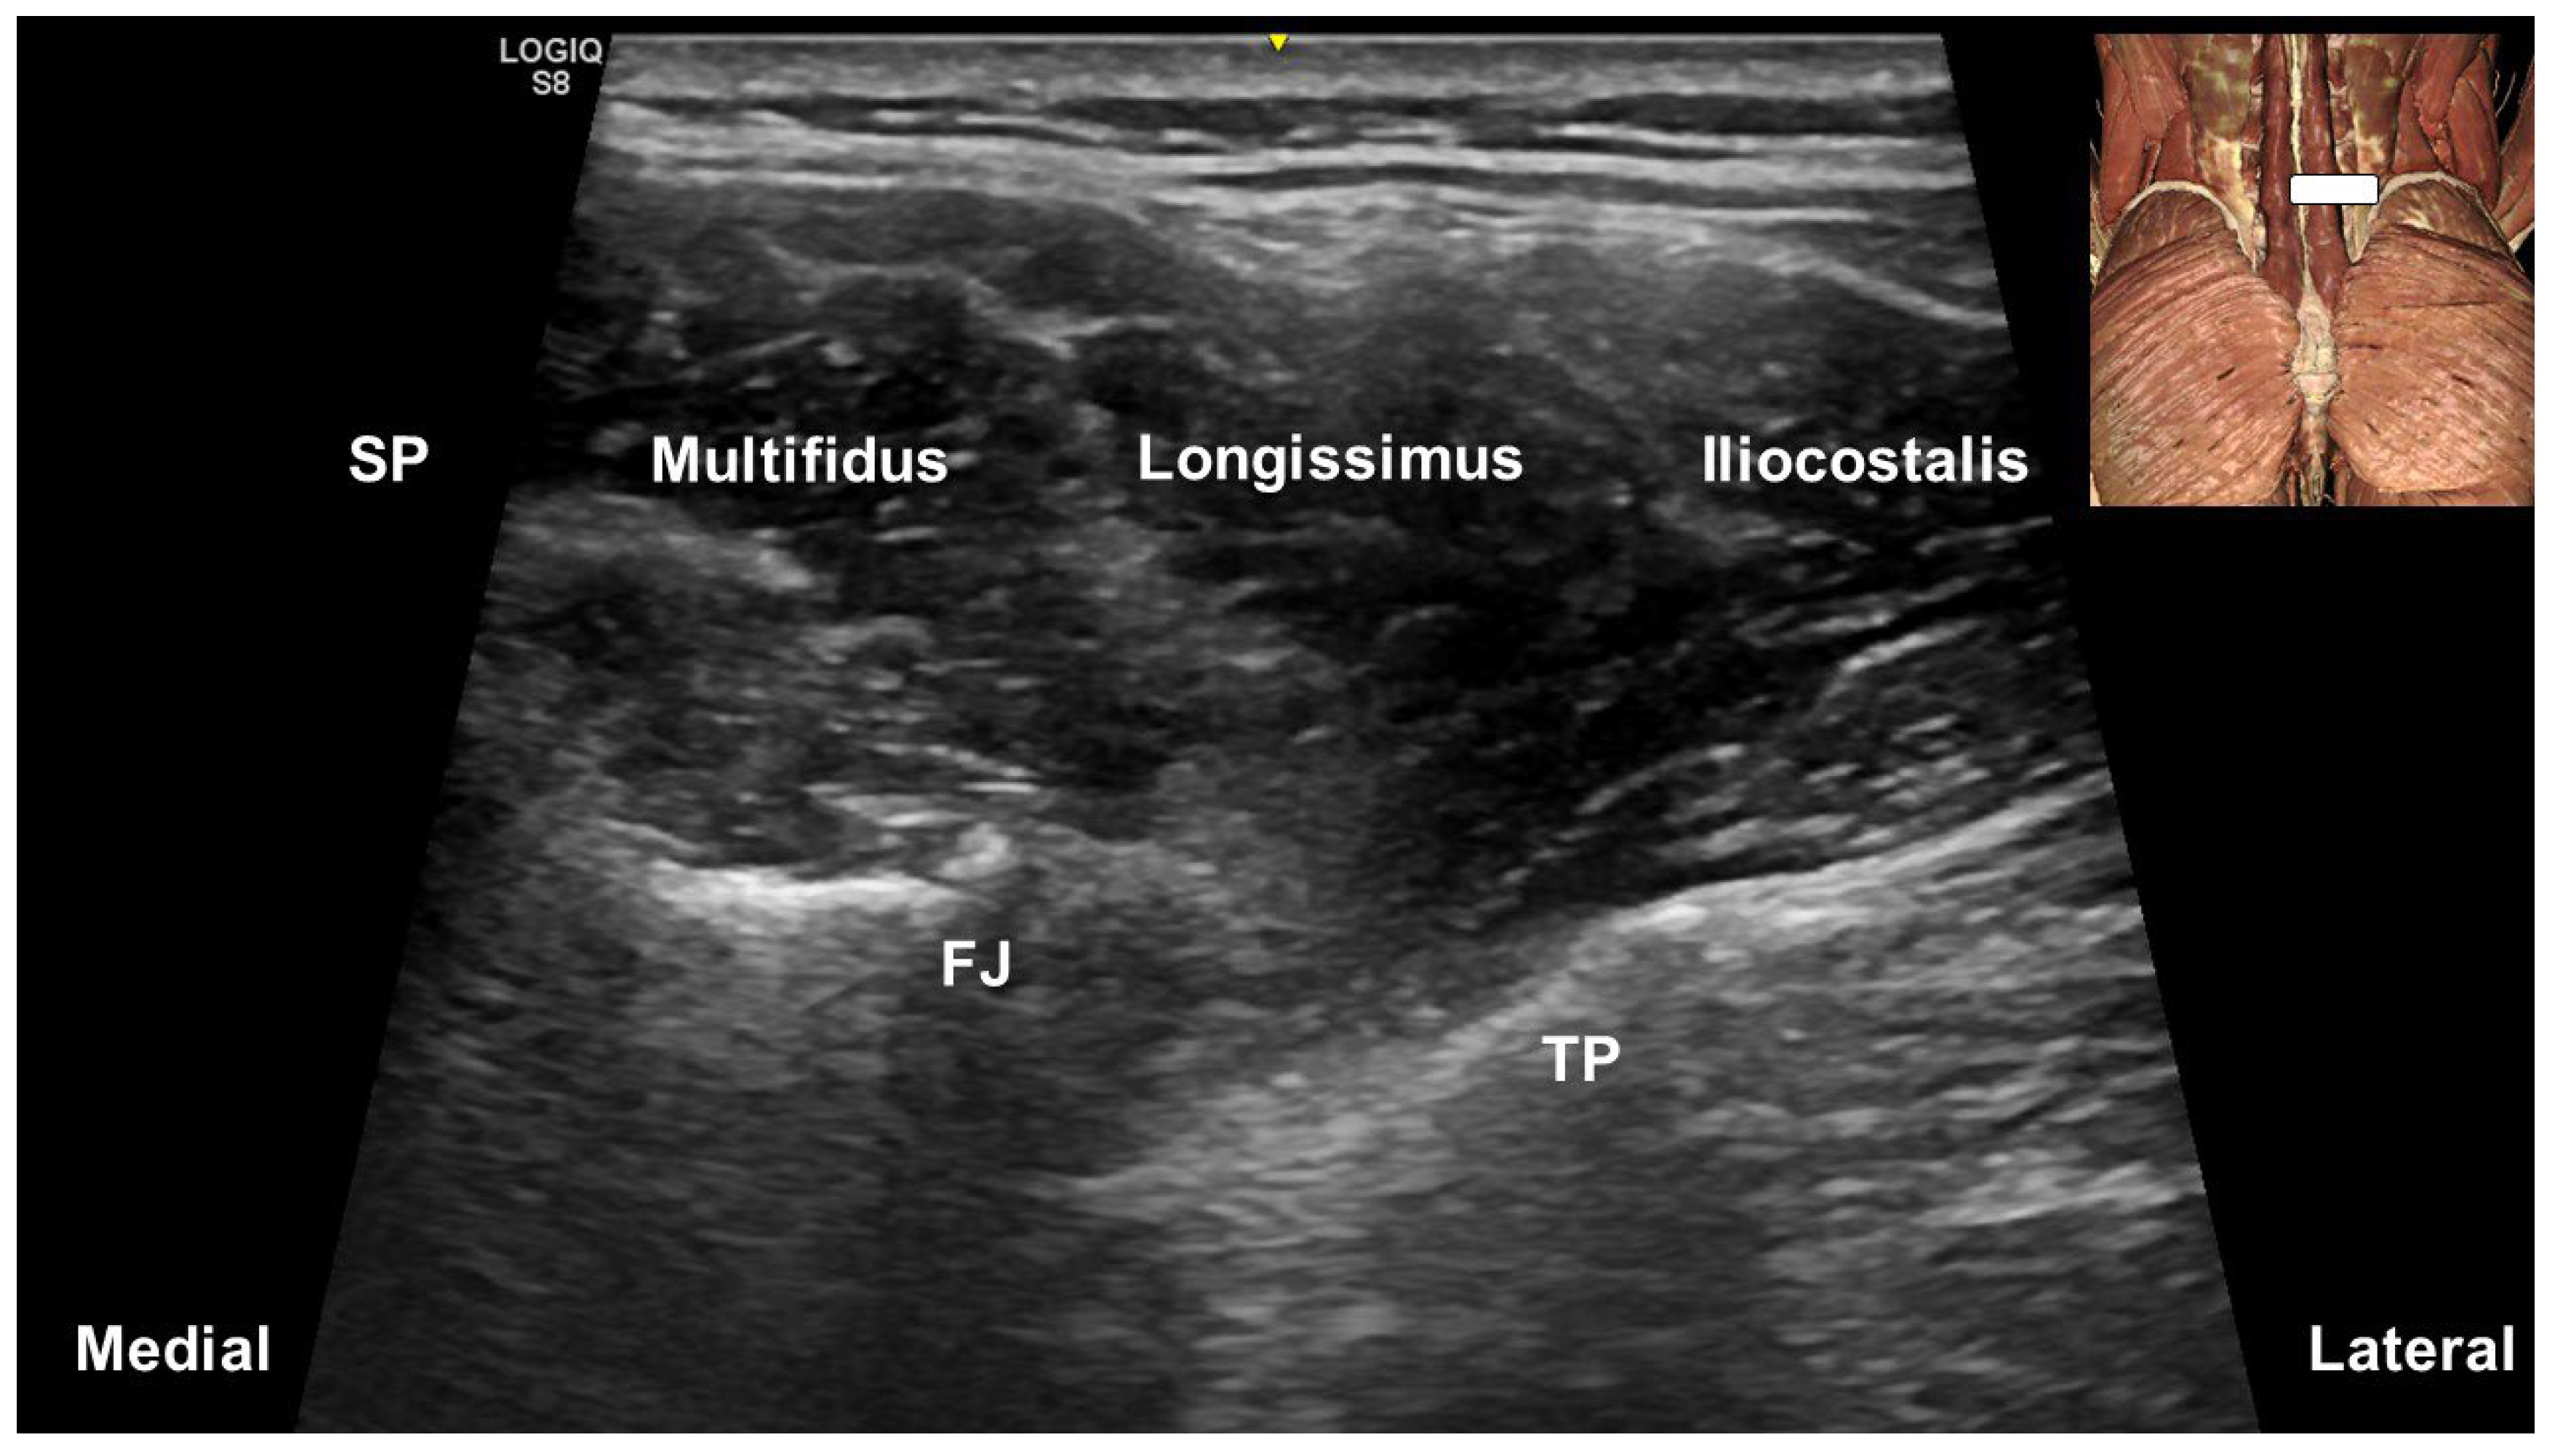

4. Multifidus Muscle and Low Back Pain

5. Ultrasound-Guided Injections Targeting the Multifidus Muscle

- Hung, C.Y.; Wang, B.; Chang, H.C.; Wu, W.T.; Liu, P.T.; Chang, K.V.; Su, D.C.; Mezian, K.; Ricci, V.; Özçakar, L. Pictorial Essay on Ultrasound and Magnetic Resonance Imaging of Paraspinal Muscles for Myofascial Pain Syndrome. Life 2024, 14, 499. [Google Scholar] [CrossRef]

- Suputtitada, A.; Chen, J.L.; Wu, C.K.; Peng, Y.N.; Yen, T.Y.; Chen, C.P.C. Determining the Most Suitable Ultrasound-Guided Injection Technique in Treating Lumbar Facet Joint Syndrome. Biomedicines 2023, 11, 3308. [Google Scholar] [CrossRef]